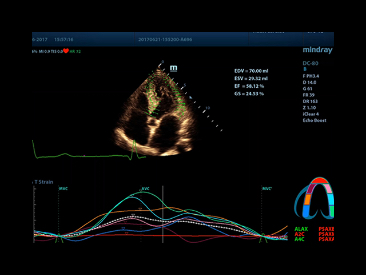

The best patient care is your ultimate goal. To achieve this requires confident diagnosis even with daily increases in patient throughput. Built on the foundation of MindrayвАЩs continuous customer insights into clinical needs and the inheritance from premium technology, the DC-80 with X-Insight is designed to help you manage your daily output with high efficiency, no matter what type patients and clinical challenges you will face.

eXceptional intelligence

Intelligence throughout entire workflow